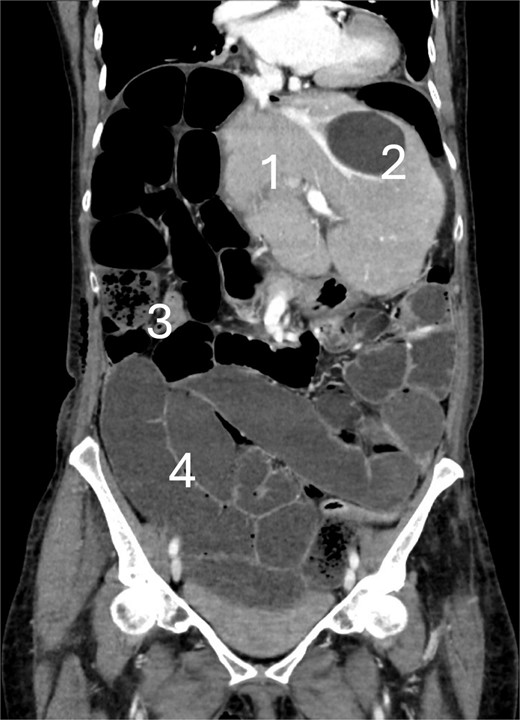

We report on a patient in her 70s with no history of abdominal surgeries, who underwent an elective open right hepatectomy for a large (11 cm) cholangiocarcinoma without signs of extrahepatic metastases. Due to an extensive centrally located tumor, an open resection was performed. The tumor was staged as pT1b. No direct mobilization of the colon was performed. On the fourth postoperative day (POD), a CT scan was conducted due to abdominal distension and absence of defecation, indicating signs of paralysis. On POD 6, the CT scan was repeated because of worsening abdominal pain and lack of clinical improvement, showing mechanical small bowel obstruction at the terminal ileum, and suspicion of cecal volvulus (Fig. 1). The patient underwent emergency laparotomy showing a cecal volvulus (Fig. 2). Intraoperatively, a pronounced mobile cecum was identified, and a right hemicolectomy was performed. Due to sepsis and the requirement for noradrenaline, a primary anastomosis was not feasible, so an end-ileostomy was performed. The patient was transferred to the Intensive Care Unit (ICU) postoperatively. During the postoperative course the patient experienced prolonged paralysis, surgical site infection, bacterial contaminated ascites, and fascial dehiscence. The patient was discharged at POD 42. The patient was doing fine 3 months after surgery.

CT scan at the 6th postoperative day after hepatectomy showing cecal volvulus with: (1) Remnant liver, (2) benign liver cyst, (3) small bowel feces sign, and (4) fluid-filled dilated small bowel.

Intraoperative photo showing the cecal volvulus with: (1) distended small bowel due to mechanical bowel obstruction, (2) rotated and distended cecum, and (3) appendix.